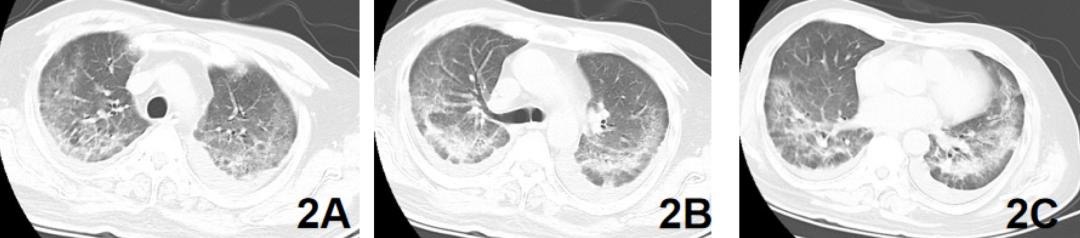

继续原治疗,3天后甲强龙40mg 由bid变为qd,3月18日复查肺CT肺部影像有吸收【图2】,呼吸困难缓解,动脉血氧恢复正常。血气分析:pH7.49 ,PO2 86mmHg,PCO2 35mmHg。停用甲强龙(共用6天),其他治疗不变,奥司他韦用药第7天停用。于3月23日复查肺CT,较入院时肺CT影像明显吸收【图3ABC】。

【图2】2020.3.18肺部CT吸收,距图1间隔4天;